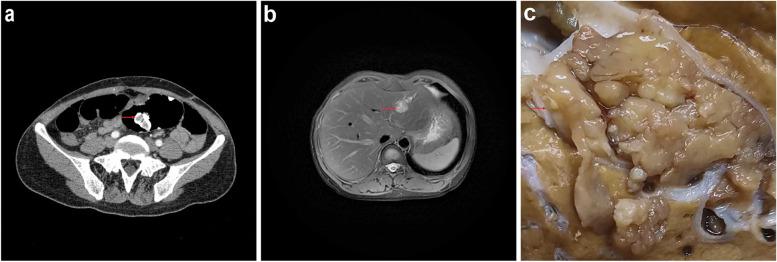

We herein describe the case of a 44-year-old woman who presented as polyps in the intestinal lumen of sigmoid colon and a 3.1 × 2.1 cm mass in the left lobe of liver. Gross feature revealed a cystic papillary mass and the neoplasm had a clear boundary with the surrounding liver tissue. Histology revealed complex papillary structures, a small amount of fine fibrovascular cores and immunohistochemistry showed extensive positive for MUC5AC, MUC6, CD117. Therefore, histological and immunohistochemical examination of the liver tumor suggested the diagnosis of IOPN. Next-generation sequencing (NGS) revealed other than STK11 germline mutation, the tumor also harbors GNAS somatic mutation at codon 478 and EGFR amplification.

我们在此描述了一位 44 岁女性的病例,其表现为乙状结肠肠腔内息肉和左肝叶 3.1×2.1cm 肿块。大体特征显示为囊性乳头状肿块,肿瘤与周围肝组织界限清楚。组织学显示复杂的乳头状结构,少量精细的纤维血管核心,免疫组织化学显示广泛的 MUC5AC、MUC6、CD117 阳性。因此,肝肿瘤的组织学和免疫组织化学检查提示 IOPN 的诊断。下一代测序(NGS)显示除了 STK11 种系突变外,肿瘤还存在 GNAS 体细胞突变 478 密码子和 EGFR 扩增。